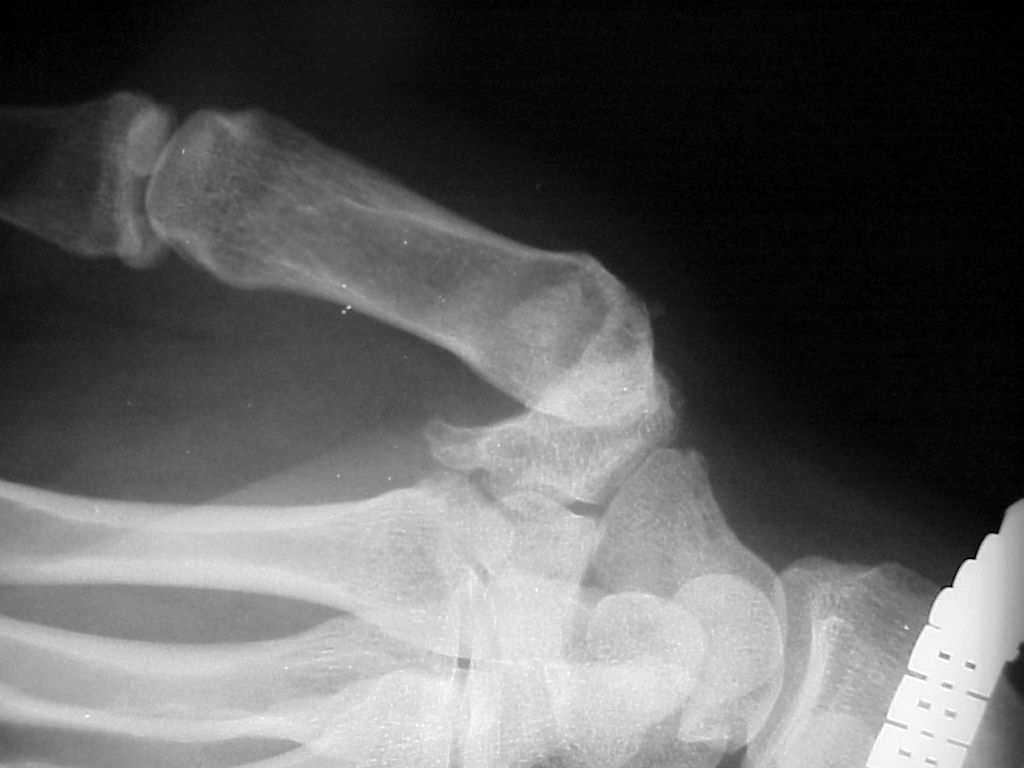

Before surgery, subluxation of the metacarpal base:

Same thumb after surgery, the reconstructed joint visible as an even space around the metacarpal base.